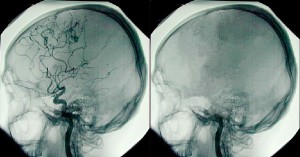

“Хадасса” атты иерусалимдік емханада аталмыш құбылысты толыққанды зерттеу үшін қарапайым адамдардың бастарынан өткен клиникалық өлімдер мен ажалдан аман қалған 7 жағыдай алынып отыр. Бұл сәтті басынан өткергендердің барлығының айтуына қарағанда, өткен жағыдайлар белгілі бір уақыт аясына сәйкес келмейді және сол сәтте болған оқиғаға қатысқан адамдардың барлығының сезімдерін сезіне алады екен. Гипоксия әсерінен туындайтын түс секілді көріністер – адамның есте сақтау қабілетіне жауап беретін ми бөліктеріндегі қанның әлсіз айналымынан туындайды. Сонымен қатар, бұл көріністер дежавю мен қарапайым естеліктерге ұқсас келеді.

Мидың өлуі. Фото: svetnsk.ru

Мамандардың тұжырымдамасына сәйкес, өлім алдында немесе клиникалық өлім кезінде адамның көз алдынан барлық өмірінің өтуі – сау психикаға тән нейрокогнитивті механизмнің шоғырланған вариациясы әсерінен болатын құбылыс екен. Өлер алдындағы адамның өсиет айтатыны да өткен өмірнің бар картинасы көз алдына келгесін жақындарына соңғы істерін тапсыратын болуы керек.